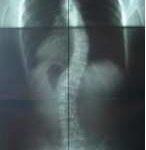

척추 측만증 치료 사례

추나요법을 위주로 하고 체형교정 바태운동을 겸하여 척추 측만증을 치료한 사례